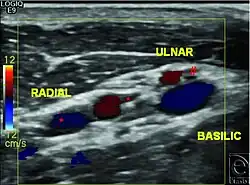

Um dies und weitere Dinge, wie die Venen und/oder Arterien im Arm des Empfängers zu untersuchen, können eine ganze Reihe von Untersuchungen wie etwa die Röntgenaufnahme, die Angiographie, die Doppler-Sonographie, die Phlebographie, oder ein CT durchgeführt werden. Die Ergebnisse dieser Untersuchungen machen die spätere Operation wesentlich besser planbar und können dazu führen, dass eventuelle Probleme schon vorzeitig erkannt werden.[31] Ein solches Problem kann zum Beispiel ein unzureichendes oberflächliches venöses Netzwerk sein, so dass im Zuge der Gefäßchirurgie eine Lösung gefunden werden muss.[32]

- Drei bis vier Venen mit einem Durchmesser, der größer als drei Millimeter ist, werden während der Mobilisation der Hautlappen frei präpariert, isoliert und dann mittels Clip verschlossen. Sollten im Unterarm nicht genügend solcher Venen vorhanden sein, müssen sie schon weiter oben (im Bereich des Oberarms, über dem Ellenbogen) gesucht werden. Diese verbindet man dann im Verlauf der Operation mit langen Venen, die dem Spender entnommen wurden und die dann nach weiter unten, zur Hand, geführt werden.[42]

- Was die Arterien angeht, präparieren die Chirurgen die Arteria radialis und die Arteria ulnaris unter Berücksichtigung der begleitenden Venen frei und durchtrennen diese dort, wo sie noch ihrem normalen, gesunden Aufbau entsprechen.[42]